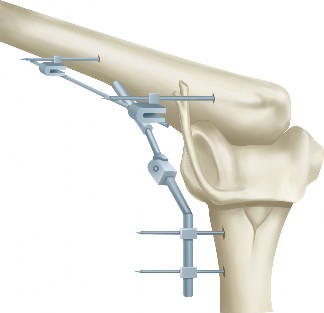

Distraction Arthroplasty:

- Indications: For painful, stiff, and unstable elbows where joint preservation is desired.

- Technique: Application of an external fixator across the elbow joint to unload the articular surfaces and maintain a gap, allowing for fibrocartilage formation. Often combined with arthrolysis.

- Outcomes: Can improve pain and ROM, but carries risks of pin tract infection, neurovascular injury, and requires prolonged external fixation. Not widely adopted due to complexity and complication profile.